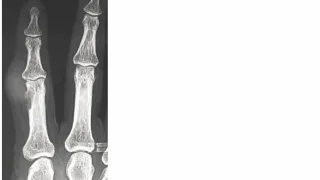

午前の病院での仕事今朝も小雨.気温は, 6 ℃.8時前に病棟に上がって, 昨日後輩医師の執刀で関節鏡下外側半月板縫合術が行われた高校生の患者さんの経過を確認.問題なく, 今日からリハビリを開始できそうです.8時から朝の病棟回診.9時前に外来...